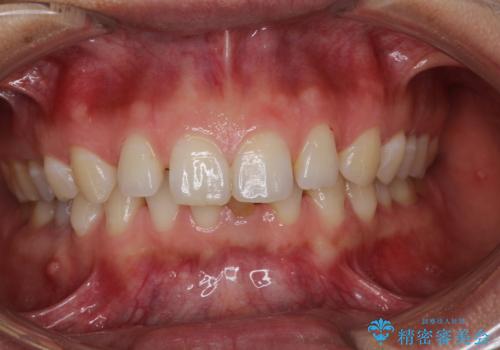

【空隙歯列】ワイヤー矯正で短期間に治療を終えたい

- 歯と歯の間に隙間があることを主訴に来院されました。

短期間での治療終了を希望され、ワイヤー矯正にて治療を行い1年ほどで治療を終了しております。

下顎前歯は矯正後補綴治療を行なっております。